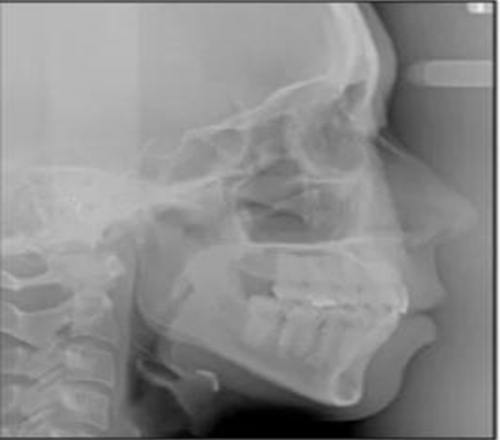

治療后頭側(cè)數(shù)據(jù)提示:無(wú)明顯骨性變化(上頜SNA82.1°,下頜SNB74.9°),上頜前牙得到內(nèi)收,略舌傾,頦部前后位置無(wú)明顯改變,仍未凸面型(圖8,表)。將治療前后圖像重疊后結(jié)果如(圖8及圖9),24月后隨訪結(jié)果見(jiàn)圖10.